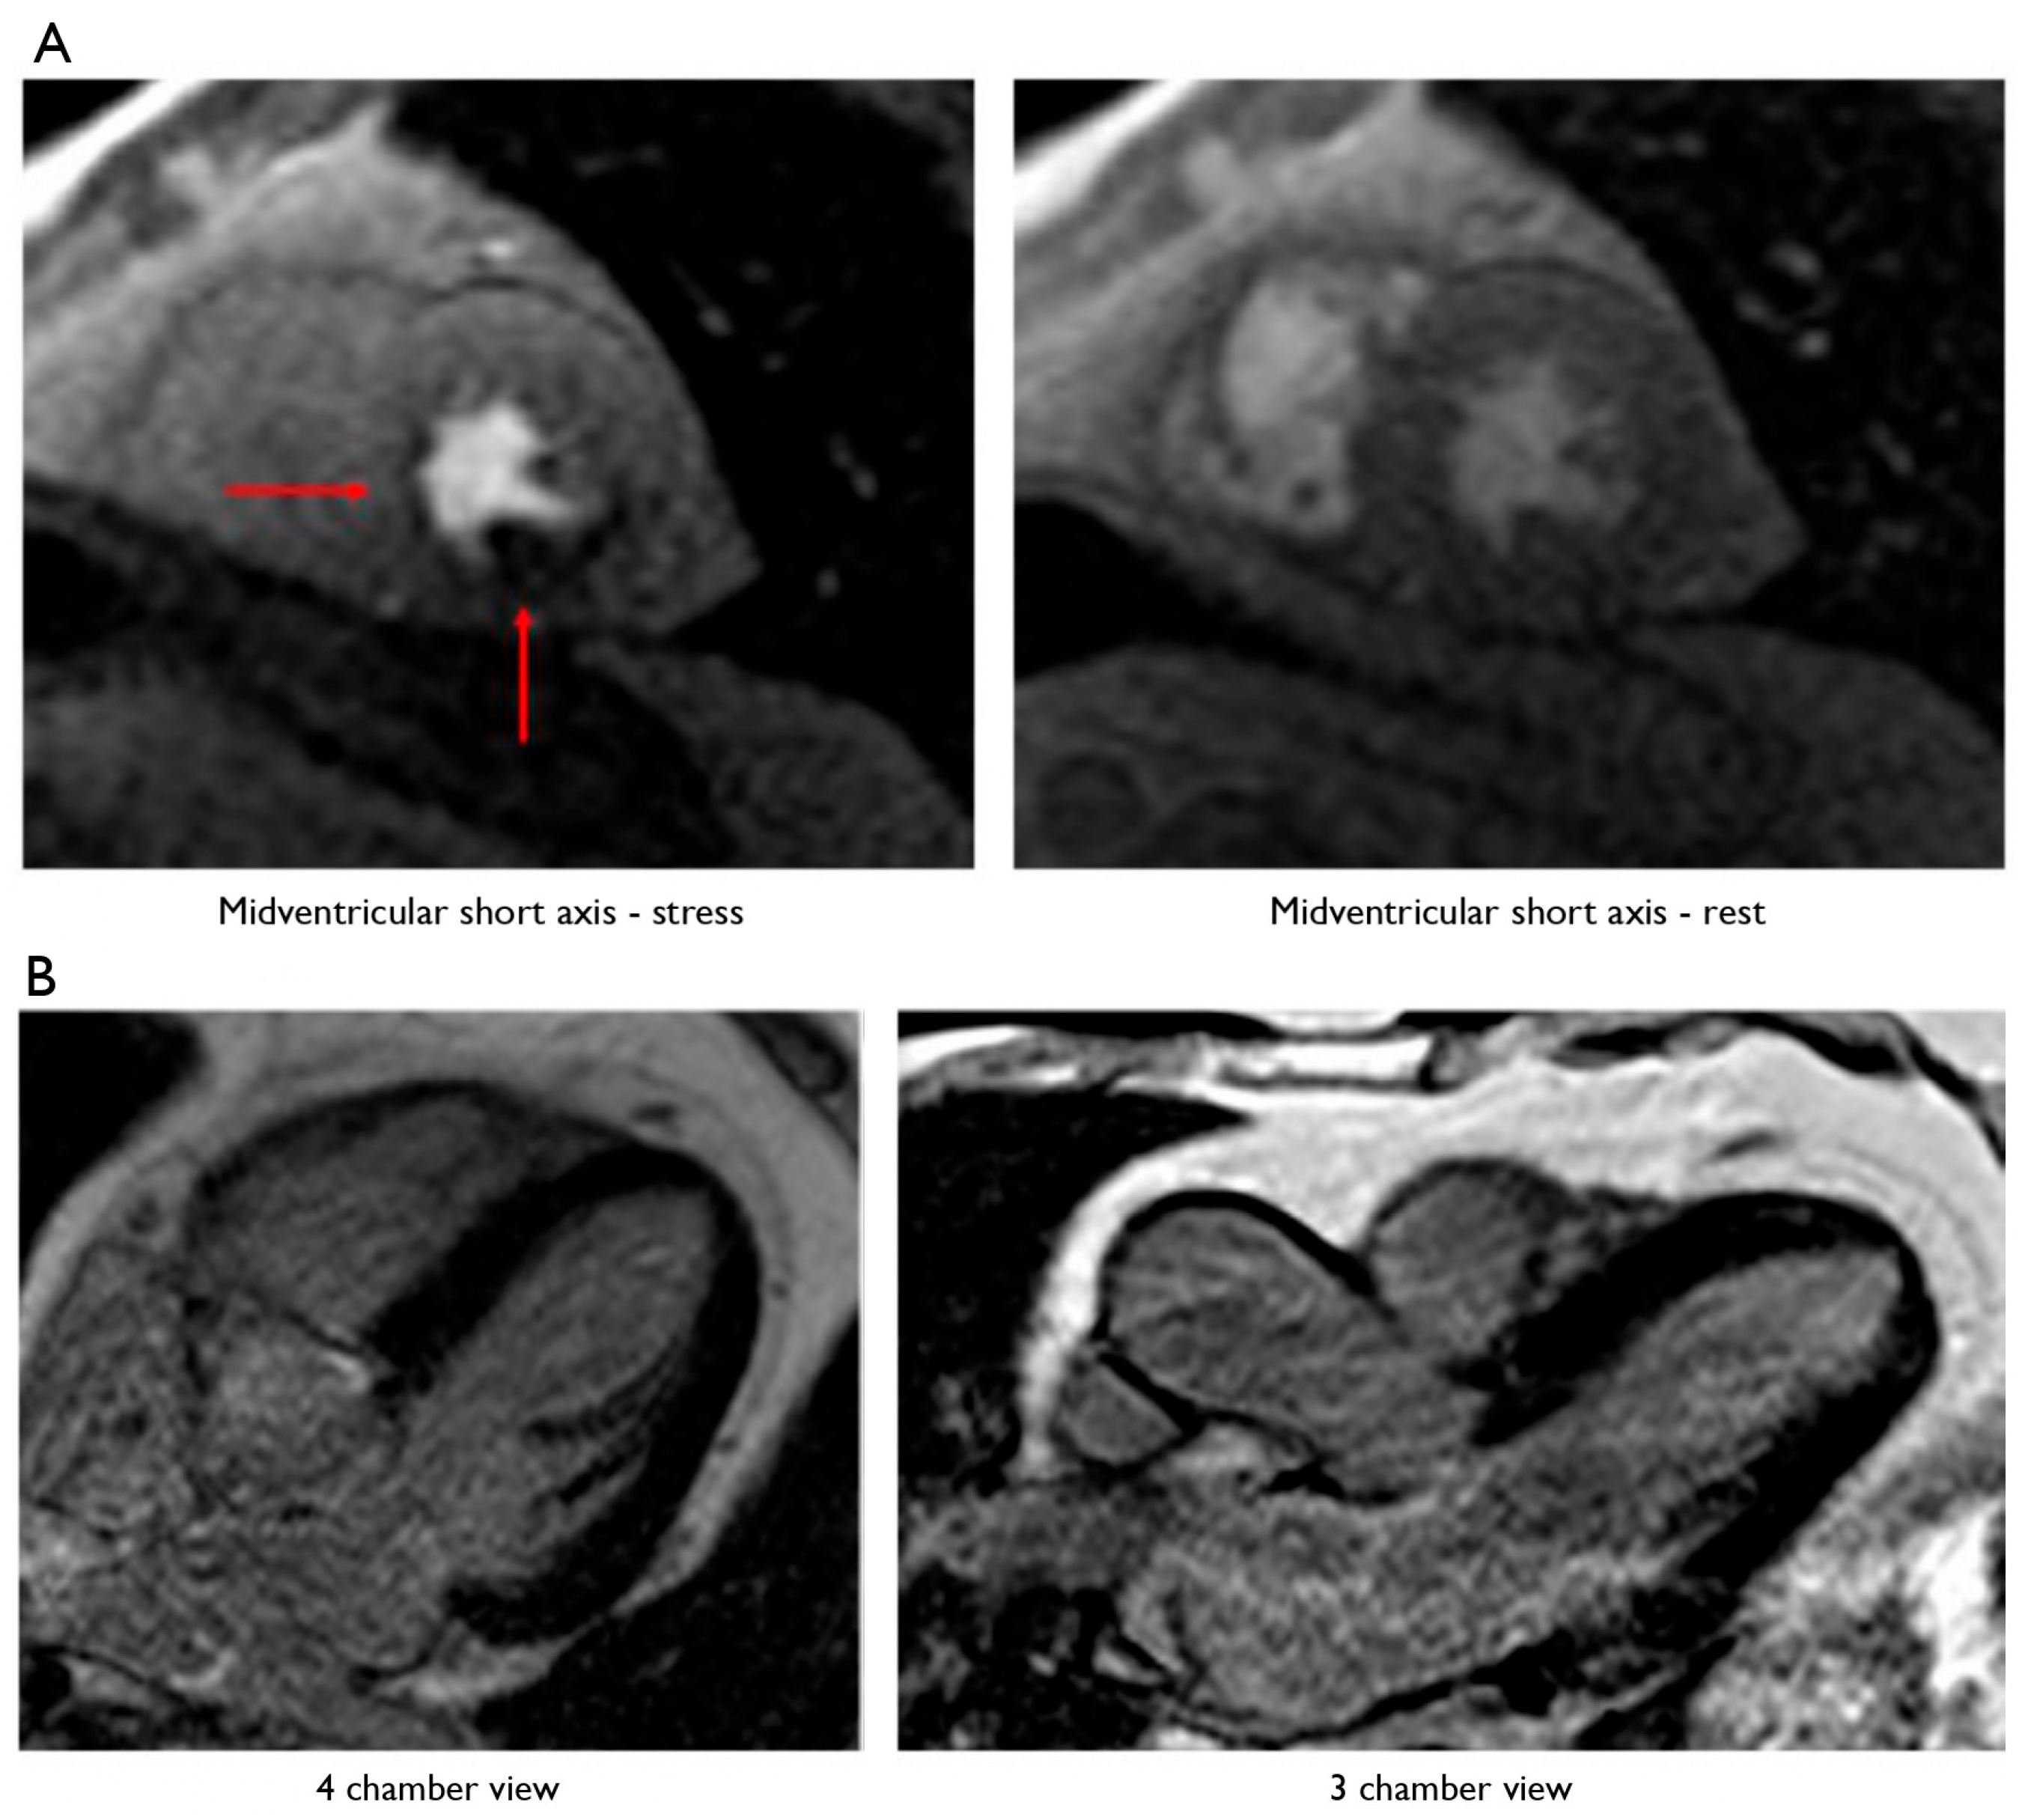

Patients showing intermediate coronary plaques at CCTA underwent S-CMR, which resulted in a positive for myocardial perfusion deficit finding in n = 17 (27%) and a negative finding in n = 45 (73%) patients (Figure 2).

Figure 2.

A 65-year-old man was admitted to our department for exertional dyspnea with onset a few months earlier. Both the 12-lead ECG and 2D-echo evaluation did not show any alterations. Considering the low–intermediate risk profile of the patient, CCTA was performed, showing an intermediate plaque on the proximal right coronary artery (RCA) and on the middle circumflex artery (CA). To evaluate their functional significance, a pharmacological stress–rest perfusion and LGE cardiac MRI with regadenoson (0.4 mg IV bolus) were performed (1.5-T MRI system). The left ventricular (LV) short-axis orientation was used for breath hold perfusion imaging, with three sections placed in the basal, midventricular, and apical regions of the LV, using a phased-array surface coil as receiver. In the stress examination, a significant subendocardial perfusion deficit was observed in the basal and middle region of the inferior wall and septum, as well as in the middle posterior wall and postero-lateral papillary muscle. No perfusion deficit was observed in the rest examination. Ten minutes later, using inversion recovery sequences, no LGE was observed. Thus, the patient underwent staged coronary angioplasty with DES placed on the RCA and CA. The patient was discharged uneventful, being free from angina at 3-year follow-up. (A) Stress–rest myocardial perfusion MRI in a patient with intermediate plaques on the right and circumflex coronary arteries. The left column shows a short-axis view at the level of the mid-left ventricle during stress (regadenoson), whereas the right column shows a short-axis view at the level of the mid-left ventricle during rest. The red arrows point to a subendocardial perfusion deficit in the middle region of the inferior wall and septum, extending to the basal segment, and in the middle posterior wall and postero-lateral papillary muscle. (B) Absence of late gadolinium enhancement (LGE) at cardiac MRI in the myocardial segments, supplied by the right and circumflex coronary arteries. The left column shows a 4-chamber view, and the right column shows a 3-chamber view: no LGE was observed.